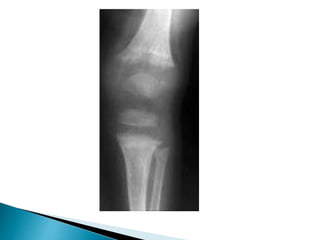

 Disappearance(closure) of this plate occurs at

different time in different bone and this is

important is identifying bone age.

 The epiphysealcartilage is responsible for the growth in length of the bone and disappears in adults.  Disappearance(closure) of this plate occurs at different time in different bone and this is important is identifying bone age.